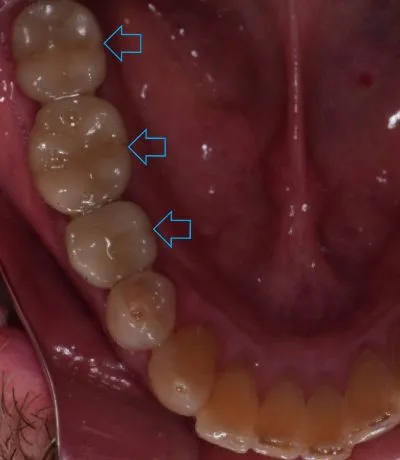

Dental implants are small titanium screws or posts placed in the jawbone where teeth are missing. Over several months, the surrounding jawbone fuses with the implant, forming a solid foundation for artificial teeth. Once the implants are integrated with the jawbone, abutments are attached. These are metal clips that connect the implant to a permanent crown, which replaces the visible part of missing teeth.

Dental implants not only replace any missing teeth with natural-looking replacement teeth, but they also help preserve the bone structure of the face and jawbone and prevent the shifting of any remaining teeth. But for most patients, the most significant advantage of dental implants is not having to worry about or care for dentures or dental bridges.

- Implants Support Remaining Teeth: If you have a gap in your teeth, the teeth on either side of your missing tooth may shift, leading to misalignment that can negatively affect our ability to eat and speak clearly. It may also lead to the need for braces to correct uneven teeth. Dental implants fill the gap for a straight smile.